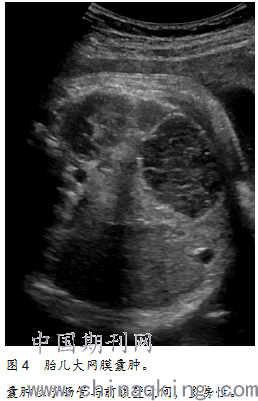

大网膜囊肿2例。位于中上腹2例;前为腹壁、后为肠管2例;单发2例;2例多次复查,大小无明显变化;类圆形1例、不规则形1例;张力较低2例;囊壁薄且轮廓不清楚2例;囊壁连续2例;囊内透声差,呈不均匀低回声,有较多纤细分隔1例;见轻微移动和变形2例(图4)。